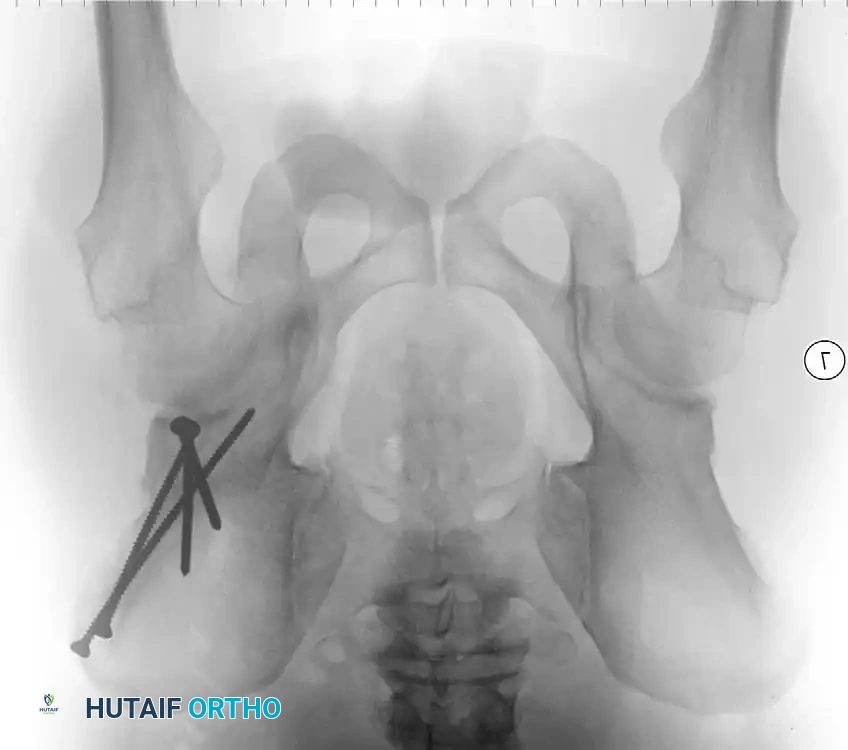

Surgical Atlas: Osteotomy and Realignment Biomechanics

The following radiographic and illustrative figures detail the preoperative planning, biomechanical axes, and intraoperative fixation strategies critical for successful osteotomies around the knee.

Preoperative templating is mandatory. The mechanical axis must be drawn from the center of the femoral head to the center of the ankle mortise. The degree of correction is calculated to ensure the new weight-bearing line passes through the targeted compartment.

Intraoperative fluoroscopy is utilized to confirm the osteotomy trajectory. Guide pins are placed parallel to the joint line, ensuring the hinge point remains intact to provide intrinsic stability to the osteotomy site.